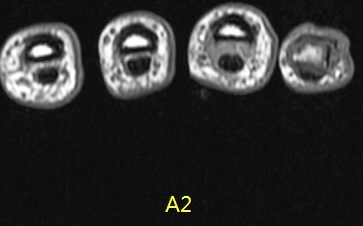

Figure 2 for case A2 pulley rupture finger (RID2437)

Figure 2

Imaging in flexion helps bring out this abnormality. The hand surgeon specifically requests it now. Also I ask the technologist to always include an adjacent normal finger for comparison.

A2 pulley rupture finger (RID2437)